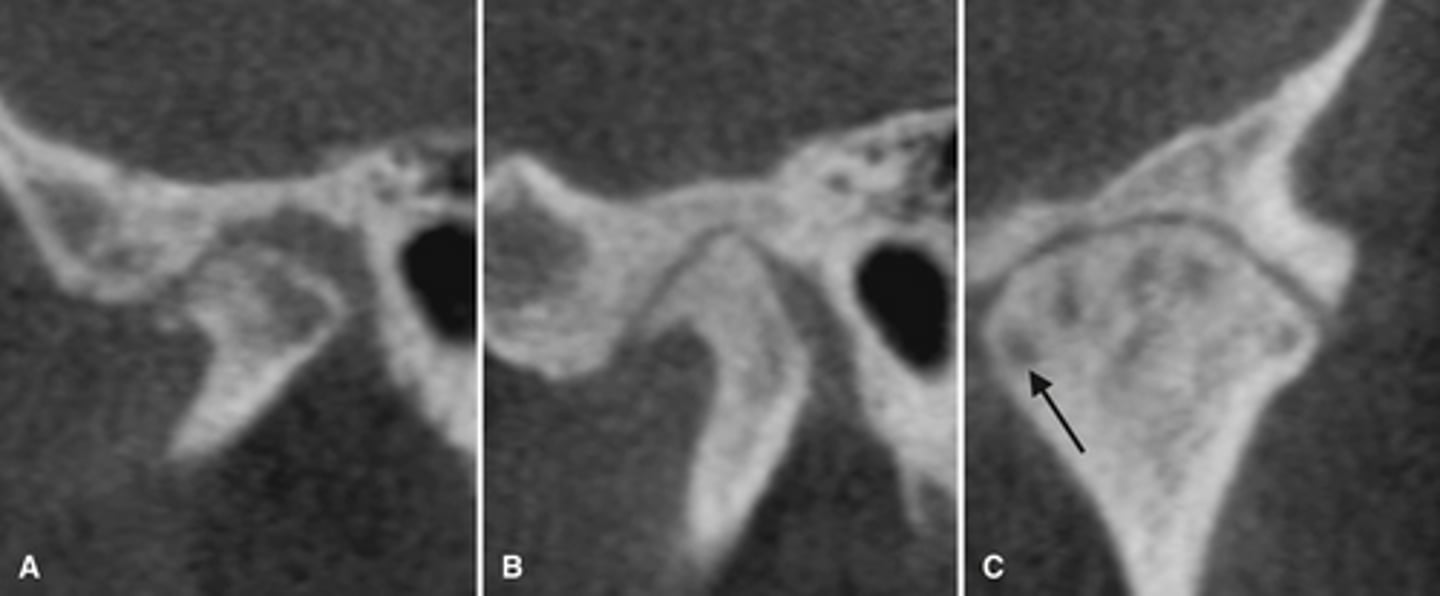

Bifid condyle

- Vertical depression in the condylar head

- often unilateral but may be bilateral

- may be a result of trauma

- some patients may have TMJ dysfunction

- Treatment isn't indicated unless pain or fxn impairment.

What is this developmental abnormality, and what is the etiology for it?